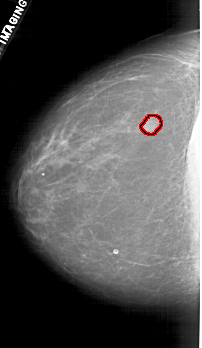

FILE: A_1880_1.LEFT_CC.OVERLAY

TOTAL_ABNORMALITIES 1

ABNORMALITY 1

LESION_TYPE MASS SHAPE LOBULATED MARGINS OBSCURED

ASSESSMENT 4

SUBTLETY 5

PATHOLOGY BENIGN

TOTAL_OUTLINES 1

BOUNDARY